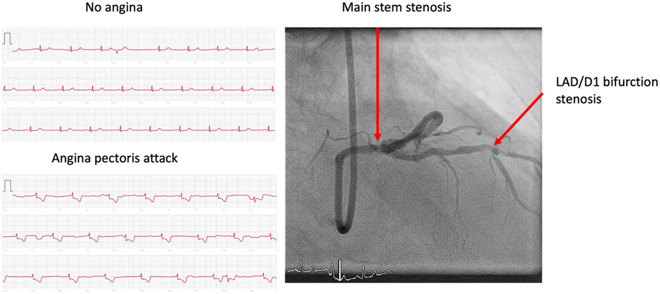

然后当这位病人向医生展示了她用Apple Watch做的ECG测试结果,其中可以看到有明显ST段抑制的追踪。医生确实在这些结果中看到了心肌缺血的证据。于是该名病人被转移到了导管实验室,最终发现存在左主干狭窄和左前降支/斜支病变。